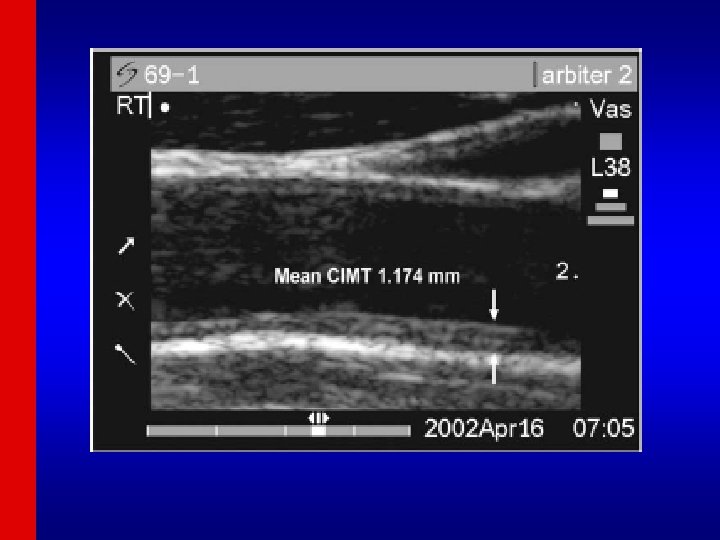

Definitions (cont. ) • SURROGATE MEASURES include: carotid intimal medial thickness (IMT), coronary calcium, angiographic stenosis, brachial ultrasound flow mediated dilatation (FMD) • Hard endpoints include myocardial infarction, CHD death, and stroke

Cardiovascular Health Study • 5, 201 Medicare eligible individuals aged 65 -102 at baseline enrolled beginning 1992 at six field centers. • Assessment of newer and older risk factors. • Ongoing follow-up of cardiovascular events and mortality • Subclinical disease measures included: – carotid B-mode ultrasound for carotid IMT at Year 2, Year 7, and Year 11 – m-mode echocardiographic measures of left ventricular mass and dimensions, left atrial dimension done at baseline (Year 2) (at UC Irvine) and follow-up (Year 7) examinations. – Ankle brachial index (ABI) for measurement of PAD – Pulmonary function (FVC and FEV 1)

Cardiovascular Health Study: Combined intimal-medial thickness predicts total MI and stroke Cardiovascular Health Study (CHS) (aged 65+): MI or stroke rate 25% over 7 years in those at highest quintile of combined IMT (O’Leary et al. 1999)

Multiethnic Study of Atherosclerosis • 6, 814 adults aged 45 -80 enrolled at 6 field centers, including Caucasians, African. Americans, Hispanics, and Chinese beginning 2000. • Extensive assessment of standard and novel risk factors, unique blood cohort among 1000 subjects. • Multiple evaluations of carotid IMT, ABI, and coronary calcium. Ancillary studies of LV size and extracoronary measures of calcification (Harbor-UCLA) and abdominal aortic calcium (UC San Diego) in full or partial cohorts.

MESA Study Design Features Four examinations approximately two years apart, exam 5 just completed Major risk factors measured at each exam Coronary calcium measured in entire cohort at Exam 1, ½ cohort at Exam 2, ½ cohort at Exam 3, and in about 1000 pts in Exam 4. Carotid IMT measured at Exam 1 and 2 -3. Cardiac MRI measured at Exam 1 and 2 -3 Ankle Brachial Index Pulse wave analysis Endothelial function measures Follow-up for CVD events and incident DM, mortality